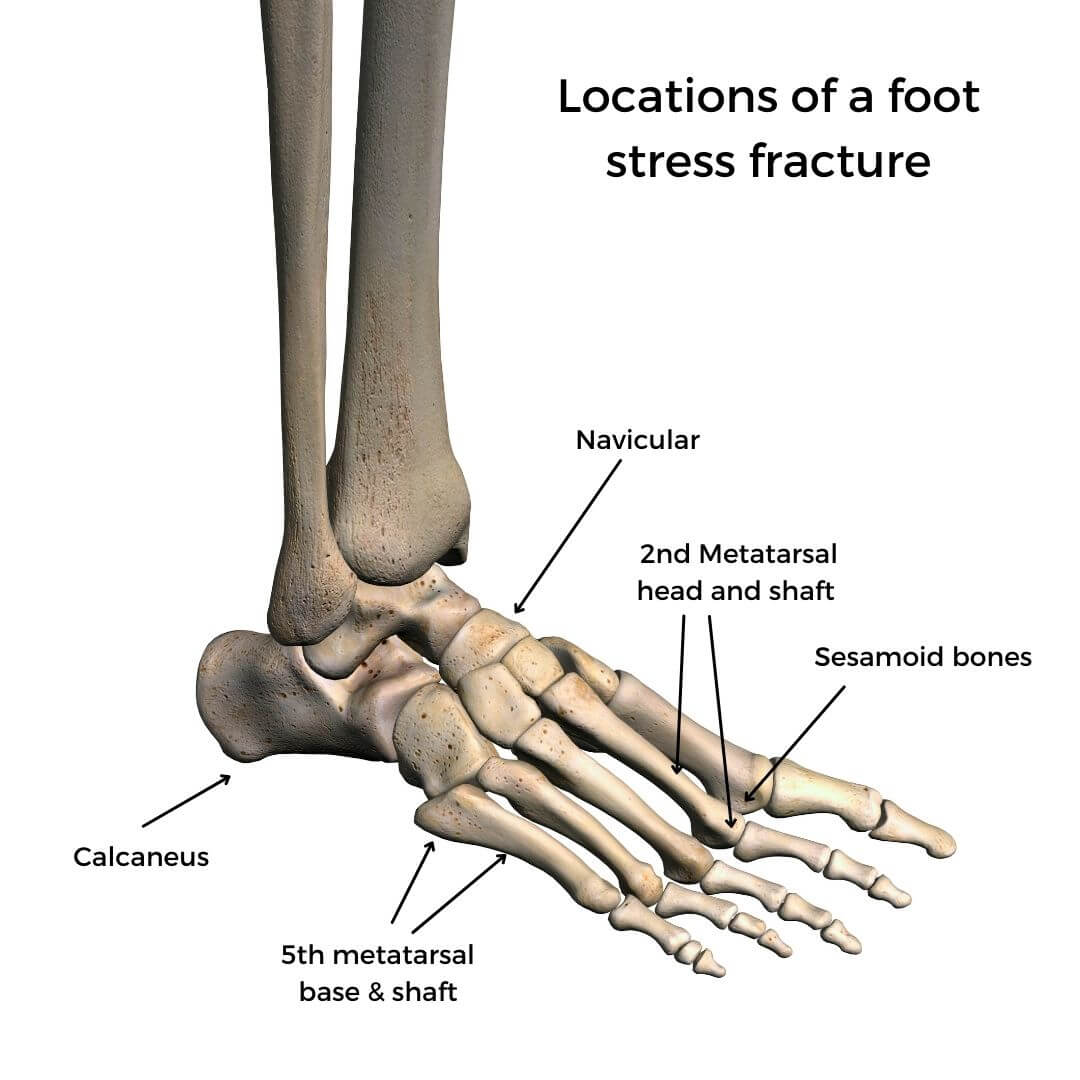

Diseases & conditions stress fractures of the foot and ankle a stress fracture is a small crack in a bone, or severe bruising within a bone. Introduction stress fractures refer to fractures occurring in the bone due to a mismatch of bone strength and chronic mechanical stress placed upon the bone. If left untreated, a stress reaction can eventually crack,.

Shin splints and stress fractures often get categorized as the same thing, panchal said, explaining that the main differences are that, while shin splints are caused by. Stress fracture should be suspected in persons with a drastic recent increase in physical activity or repeated excessive activity with limited rest. Mri is the most sensitive modality for detecting stress fracture, and may also be useful for differentiating ligamentous/cartilaginous injury from a bony injury.

36, 51 scintigraphy is able. Most stress fractures are caused by. One or more of the following diagnostic imaging exams may be used to confirm the presence of a foot stress fracture.

Point tenderness, swelling and changes in your. Bottom line a stress fracture of the foot is a tiny crack in one of the bones in your foot. Stress fractures are tiny cracks in a bone.